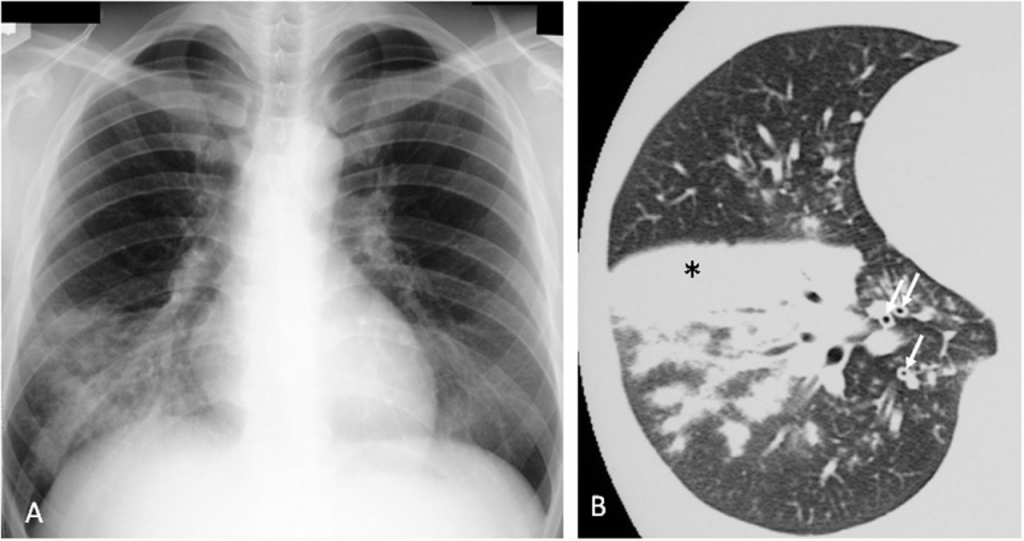

마이코플라스마 폐렴 환자의 30~40%에서 구토, 복통, 피부 발진 등의 '폐가 아닌 부위의 증상'이 나타난다. 방사선 검사상 소견은 대개 간질 폐렴이나 기관지 폐렴으로 나타나며 주로 폐의 하엽(아랫부분)이 많이 침범된다.